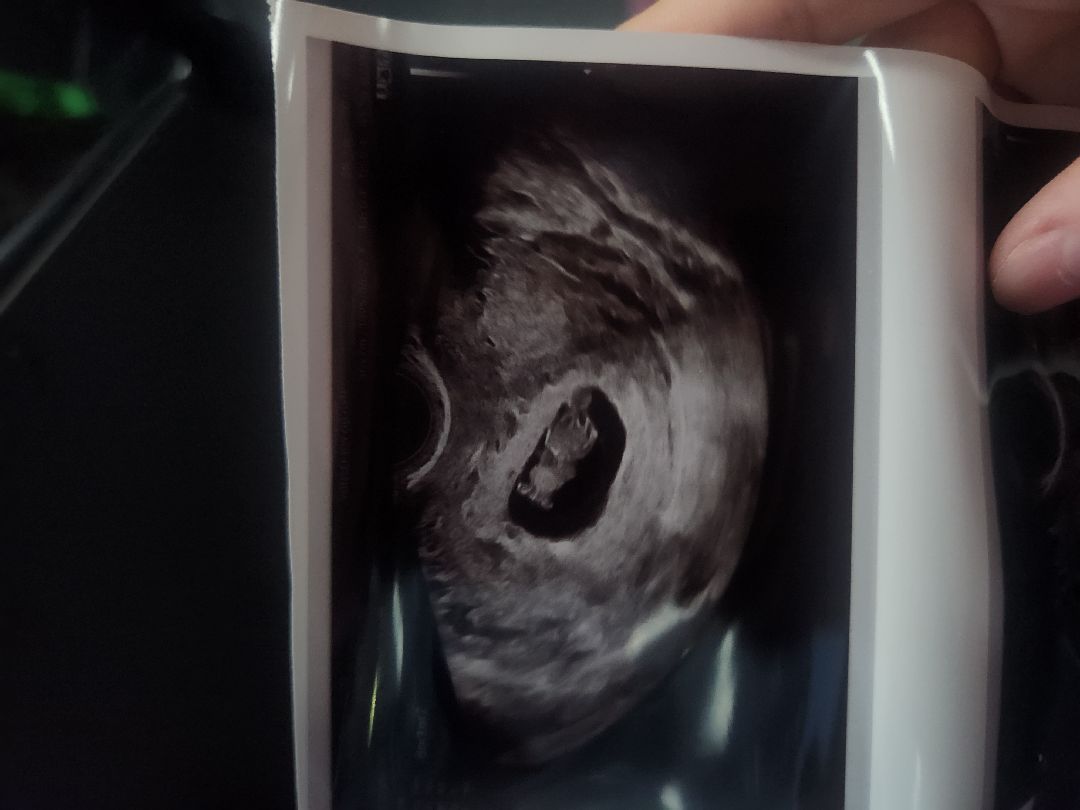

9주차 젤리곰봤을때 태아 움직임 있었나요?

9주차 접어들어 촘파 보고왔는데 저는 움직임이 없어서ㅠ 괜히 불안하고 그러네요